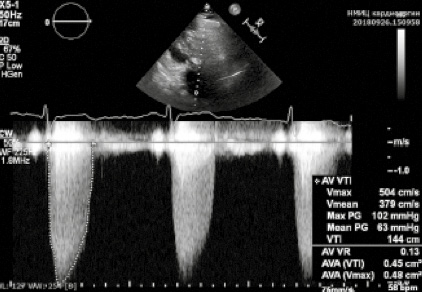

ЭхоКГ. Гипоакинез нижней и большей части задней стенки левого желудочка (ЛЖ). Фракция выброса ЛЖ – 43%. Выраженный кальциноз АК, максимальный систолический градиент 102 мм рт. ст., средний – 63 мм рт. ст.; площадь раскрытия по уравнению непрерывности – 0,4 см2 (рис. 2).

Рис. 2. Измерение транспротезных систолических градиентов на АК.